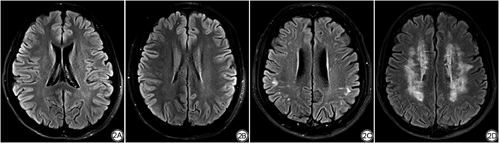

依据T2-FLAIR图像,采用Fazekas量表对所有受试者的DWML分布情况进行判断[18]。Fazekas量表评估DWML的内容如下:(1) 0分:无病变;(2) 1分:点状病变;(3) 2分:病变开始融合;(4) 3分:病变大面积融合(图2)。按照Fazekas量表的量化标准,由两名有经验的放射科医生分别独自依据Fazekas量表完成DWML的评估,当两名医生意见不一致时,共同讨论后得出受试者脑白质评分结果。由于该研究受试者均为健康青年志愿者,因而脑白质病变并不严重,最终人群中只有0分和1分两种评分结果。因此,依据受试者有无皮层下DWML将其分为两组,分别为DWML组和无DWML组(non-deep white matter lesions,N-DWML),其中DWML组共计53人,N-DWML组共计111人。